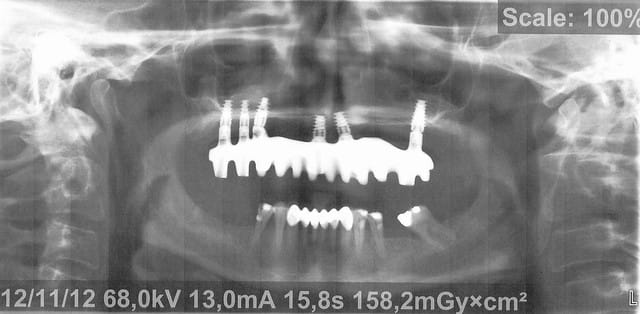

Voici donc les panos pour vos petits yeux ébahis

Profitez bien : elles sont ds l ordre chronologique...

- On y voit un manque flagrant de densité du greffon

- On y voit une perte d'un implant sans changement de plan de traitement, on se retrouve avec un seul implant du coté où mastique le patient

- On y voit une armature qui baille sur le seul implant qui reste secteur 2, et donc manque de passivité

- On y voit ce qui devait arriver,

Mais je vois aucun rapport entre l’échec et la nature du matériau mis en place dans le sinus....

C est bien ça Cngulum tu es le premier à voir tout ce qui se voit sans avoir besoin de dire que les panos sont floues

Mais je persiste et je te dis que la nature du BioOss pose problème ds tous je dis bien tous les sinus lifts et même les autre endroits